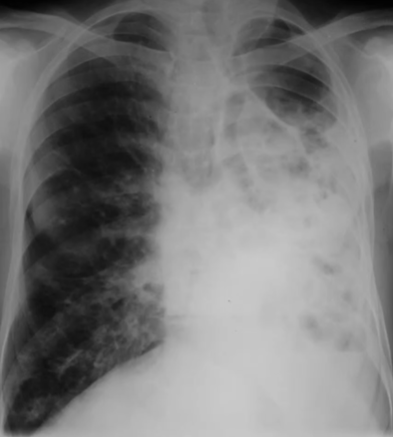

Rx toracică, incidență P-A

DESCRIERE:

la niv. întregului hemitorace drept → opacitate extinsă, nesistematizată, de intensitate mare, omogenă

caracter expansiv → împinge traheea și mediastinul de partea opusă

diafragm deplasat în jos

lărgirea spațiilor intercostale

umplerea spațiului costo-diafragmatic

DX: pleurezie masivă

DD: atelectazie → caracter retractil